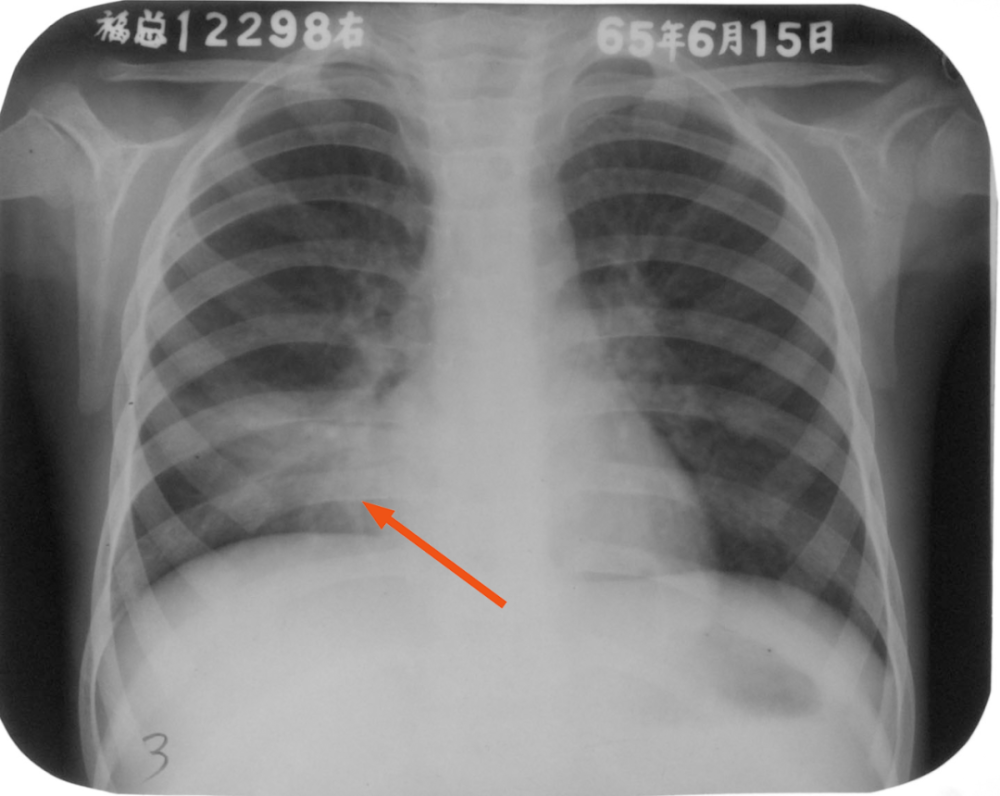

肺炎x线图片

肺炎x线图片,肺炎ct图片

大叶性肺炎x线图片

大叶性肺炎x线表现